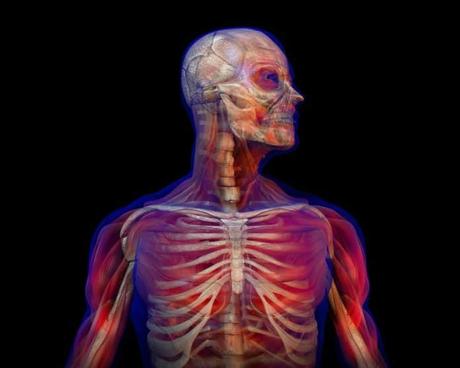

Hace unos días distintos medios publicaron una noticia en donde se aseguraba que se había descubierto un nuevo órgano. Sergio Ferrer diseccionó la investigación para Hipertextual y esto fue realmente lo que se encontró:

El artículo publicado la semana pasada en la revista Scientific Reports no hace referencia al descubrimiento de un nuevo órgano ni sugiere que el intersticio pueda ser considerado como tal. Los autores aseguran que “la anatomía y composición del espacio intersticial entre las células se entiende cada vez mejor”, si bien su localización y estructura es descrita “vagamente en la literatura científica”.

Mediante una técnica microscópica que muestra tejidos vivos en lugar de fijados, los autores describen “la anatomía e histología de un espacio lleno de líquido, previamente no identificado aunque extendido y macroscópico. Una nueva expansión y especificación del concepto del intersticio humano”. Expandido, pero no descubierto. ¿De dónde sale la idea del nuevo órgano?

El origen de la información está en la nota de prensa publicada en el servicio de noticias científicas Eurekalert!, del que se nutren medios de todo el mundo. El titular: “Un ‘órgano’ nuevo había sido omitido por los métodos estándar”. Citando como fuente a los autores, se asegura que los investigadores “han identificado una característica de la anatomía humana previamente desconocida” y que el estudio es el primero que identifica al intersticio como un órgano “por derecho propio”.

El problema es que el espacio intersticial es conocido desde hace al menos 200 años y los expertos no tienen tan claro que se pueda considerar un órgano.